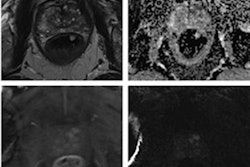

Editor's note: The image on the homepage used to introduce this topic is a T2-weighted multiparametric MRI scan performed in a 59-year-old patient presenting with dysuria and a family history of prostate cancer. Image courtesy of Dr. Olivier Rouvière, PhD.